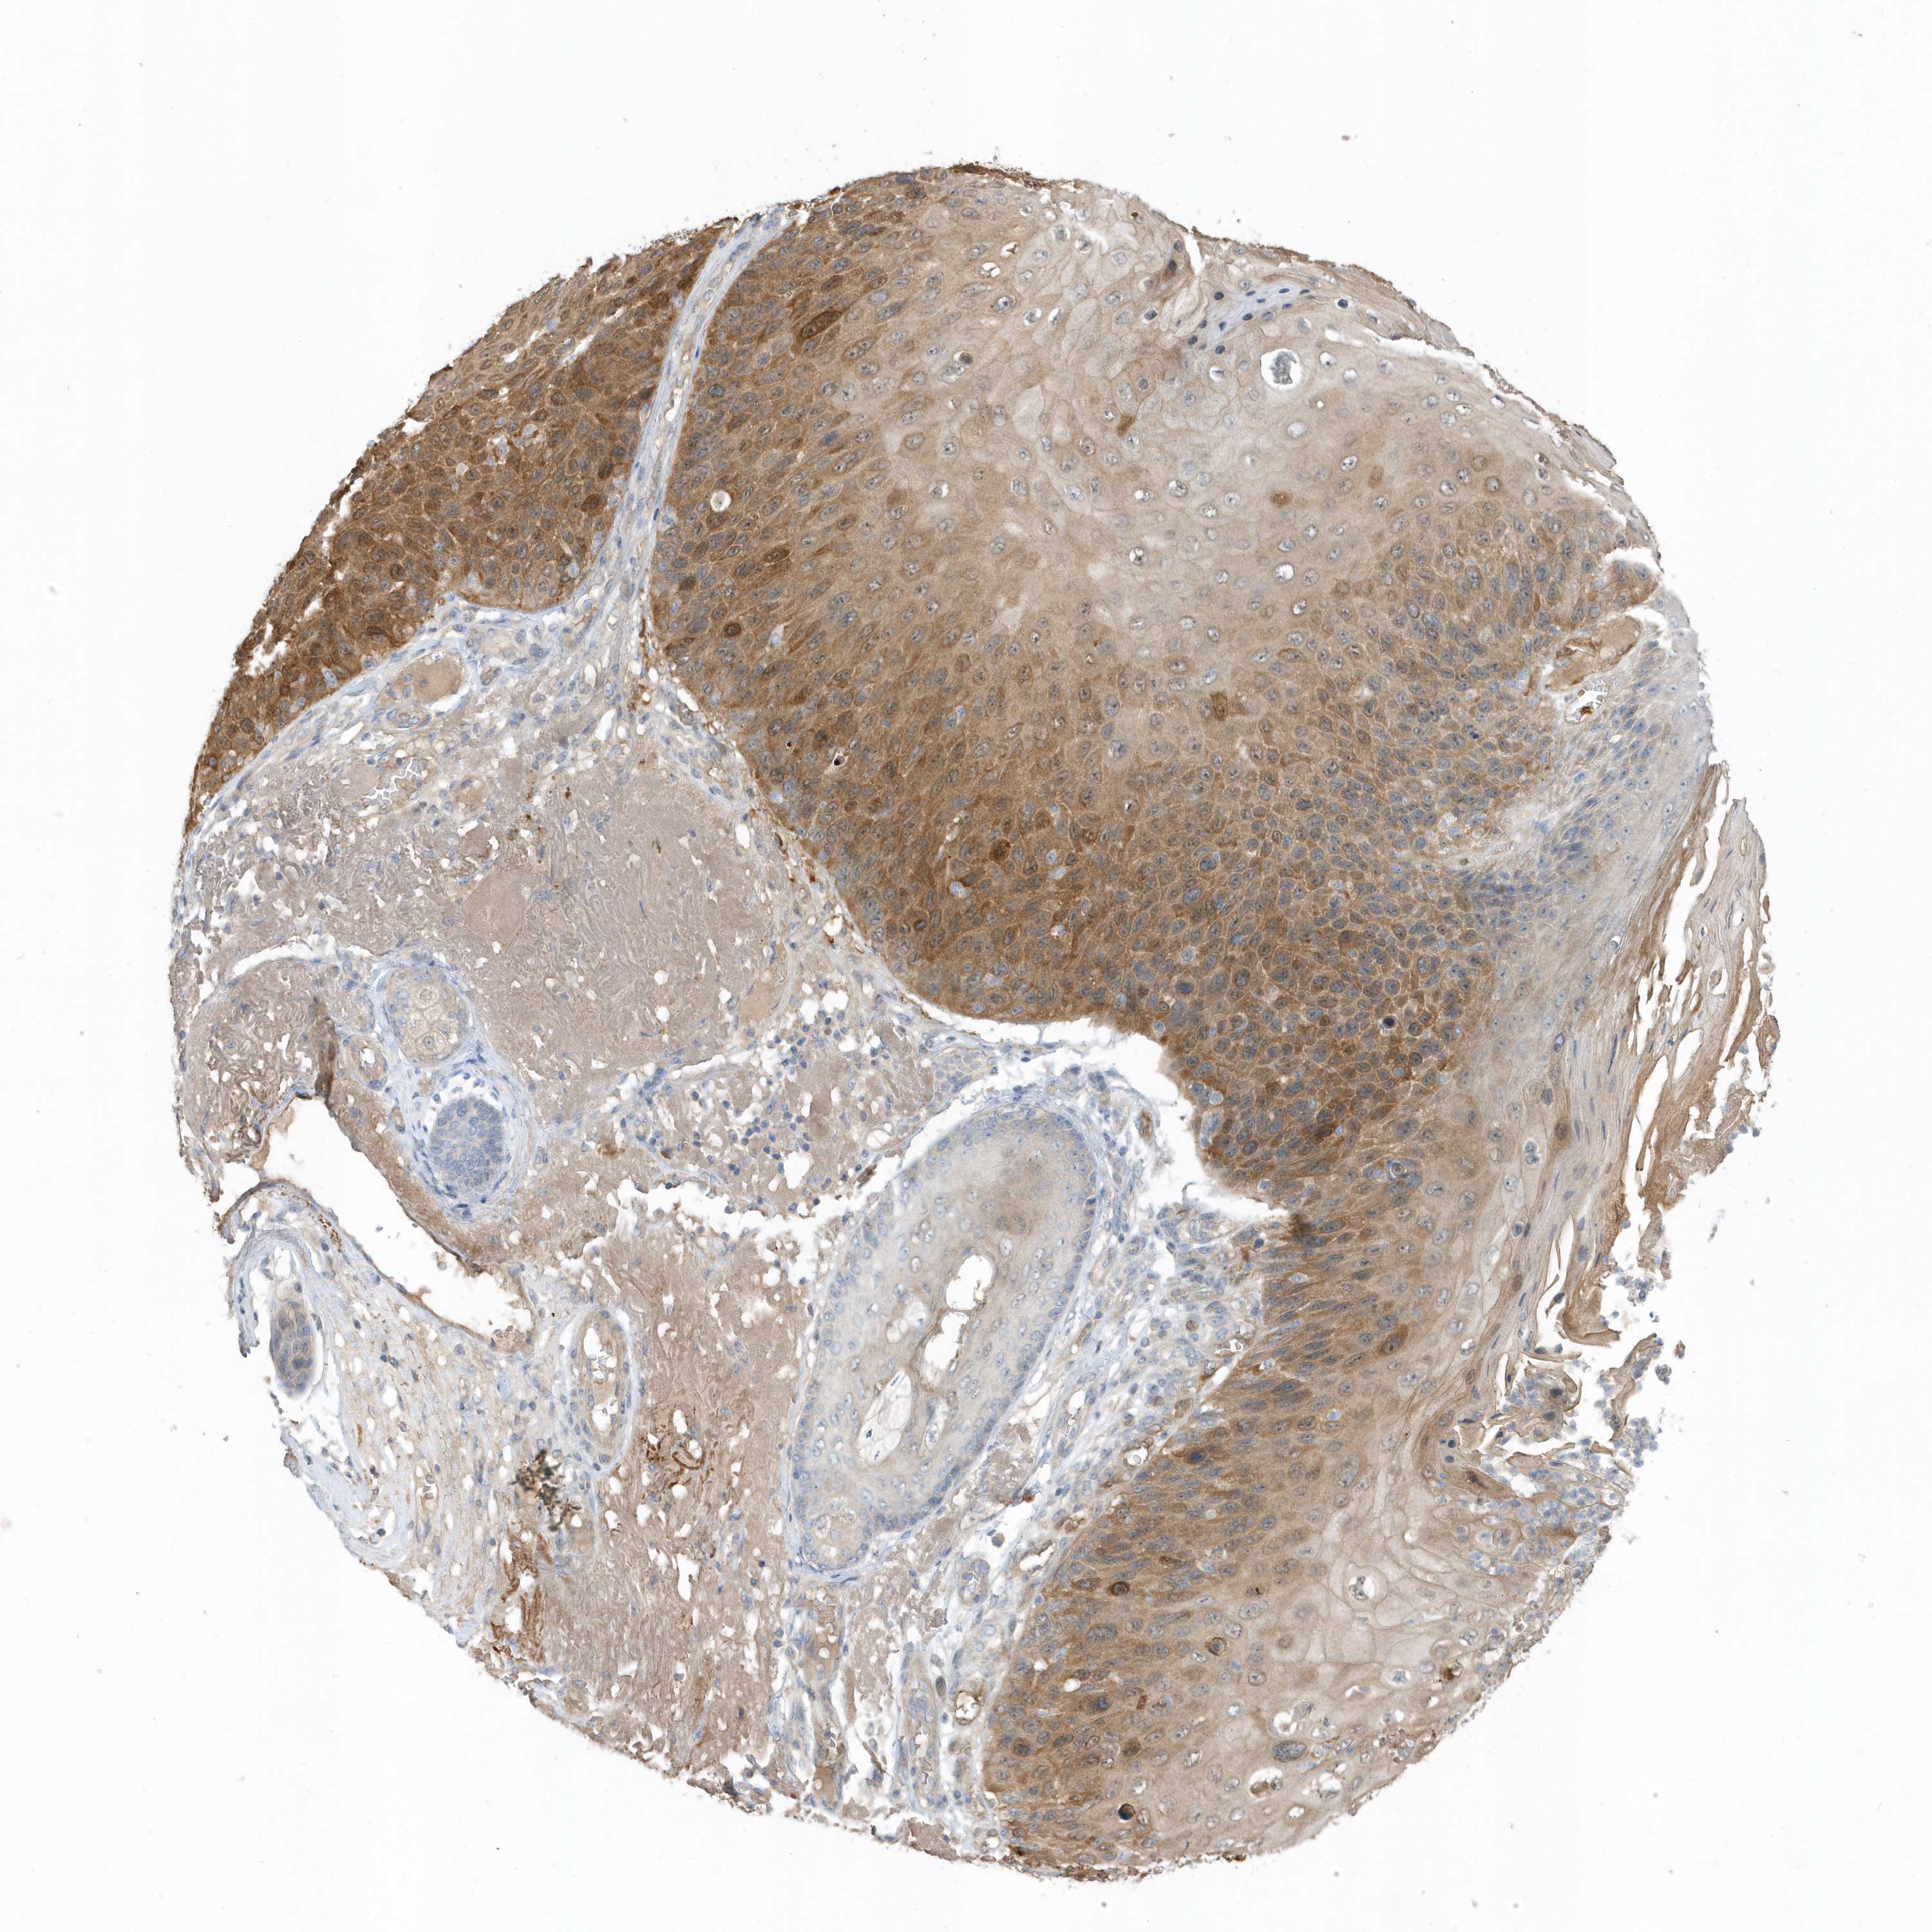

Basal cell and squamous cell cancer

SKIN CANCER - Protein expressioni

A mouse-over function shows sample information and annotation data. Click on an image to view it in a full screen mode. Samples can be filtered based on level of antibody staining by selecting one or several of the following categories: high, medium, low and not detected. The assay and annotation is described here.

Antibody stainingi

Antibody staining in the annotated cell types in the current human tissue is reported as not detected, low, medium, or high, based on conventional immunohistochemistry profiling in selected tissues. This score is based on the combination of the staining intensity and fraction of stained cells.

Each image is clickable and will lead to virtual microscopy that enables deeper exploration of all samples and also displays staining intensity scores, fraction scores and subcellular localization as well as patient and tissue information for each sample.

Antibody HPA035844

Antibody HPA035845

Staining

High

Strong

>75%

Cytoplasmic/membranous

Squamous cell carcinoma, NOS